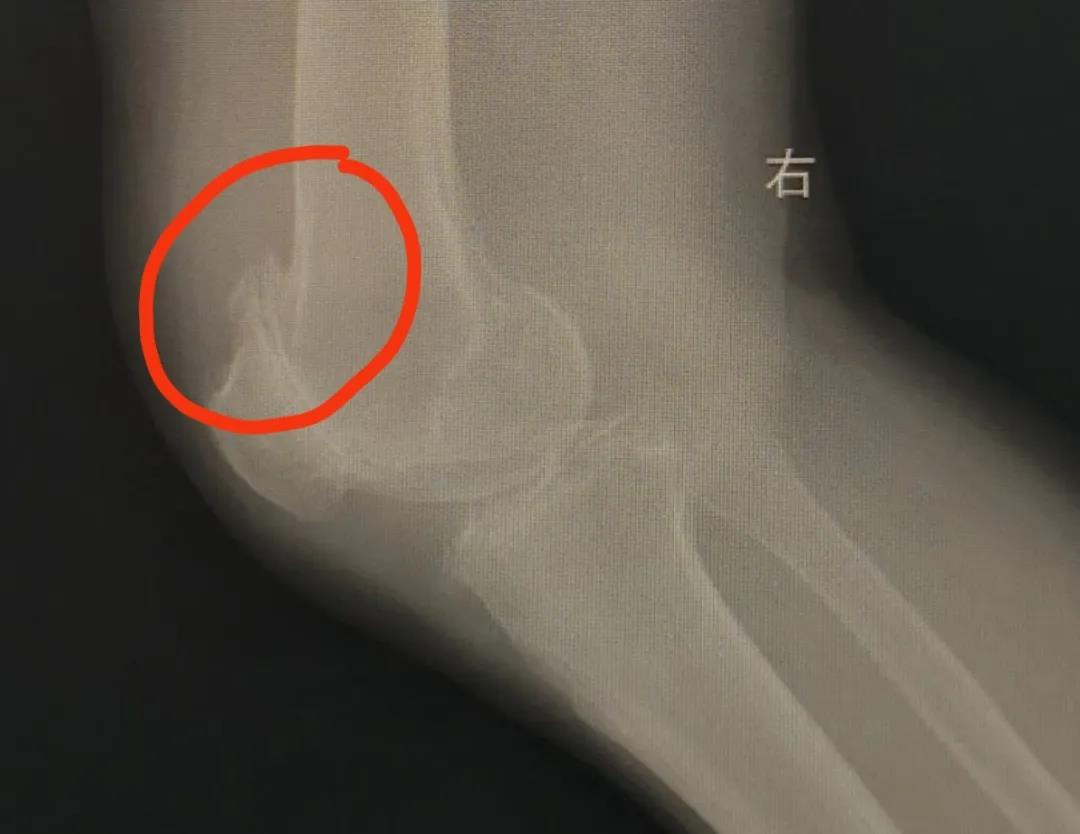

骨刺也叫骨质增生、退行性关节病等,多发于45岁以上人群,往往造成软骨磨损,进而引起关节不稳、变形、韧带松弛等。常见于足跟和膝关节。

除日常保健、中医理疗,严重者可以采用手术治疗。聚焦超声技术成为骨刺治疗的新方法。该技术可通过聚焦超声促进内源性镇痛物质释放、抑制炎性反应等达到理想治疗效果。